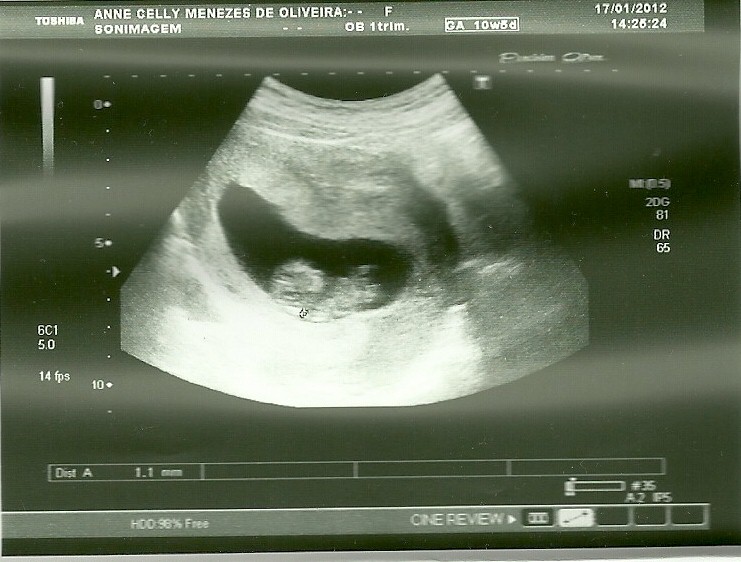

- A medida do meu bebê esta semana, da cabeça ao bumbum, deve variar entre 65 e 78mm. E o seu peso vai estar em torno de 13 e 20 gramas;

- Estou, super, hiper ansiosa para saber o sexo do bebê! Pois, então esta semana já é poss´vel identificar o sexo pela ulta sonografia, mesmo sabendo que é bem dificil pq as estruturas ainda são muito pequenas. Há uma boa chance do exame não identificar. Se eu quiser ter certeza absoluta de que o exame irá detectar se está vindo um Gianecchinni ou uma Gisele Büdchen, é melhor esperar até a 16ª semana para fazer o ultrassom. (Mas eu acho que não vou esperar não...rsrsrs)